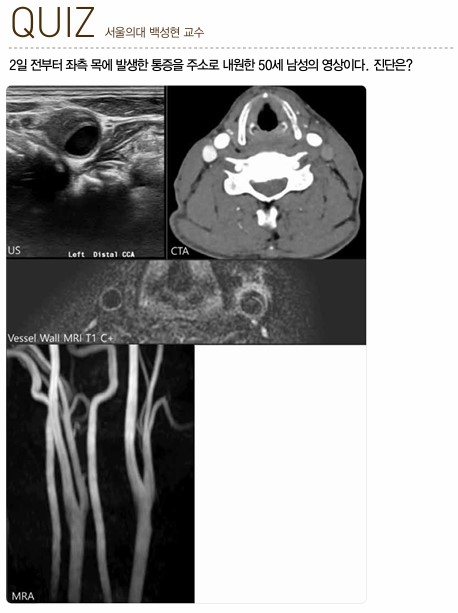

Radiology V20N3